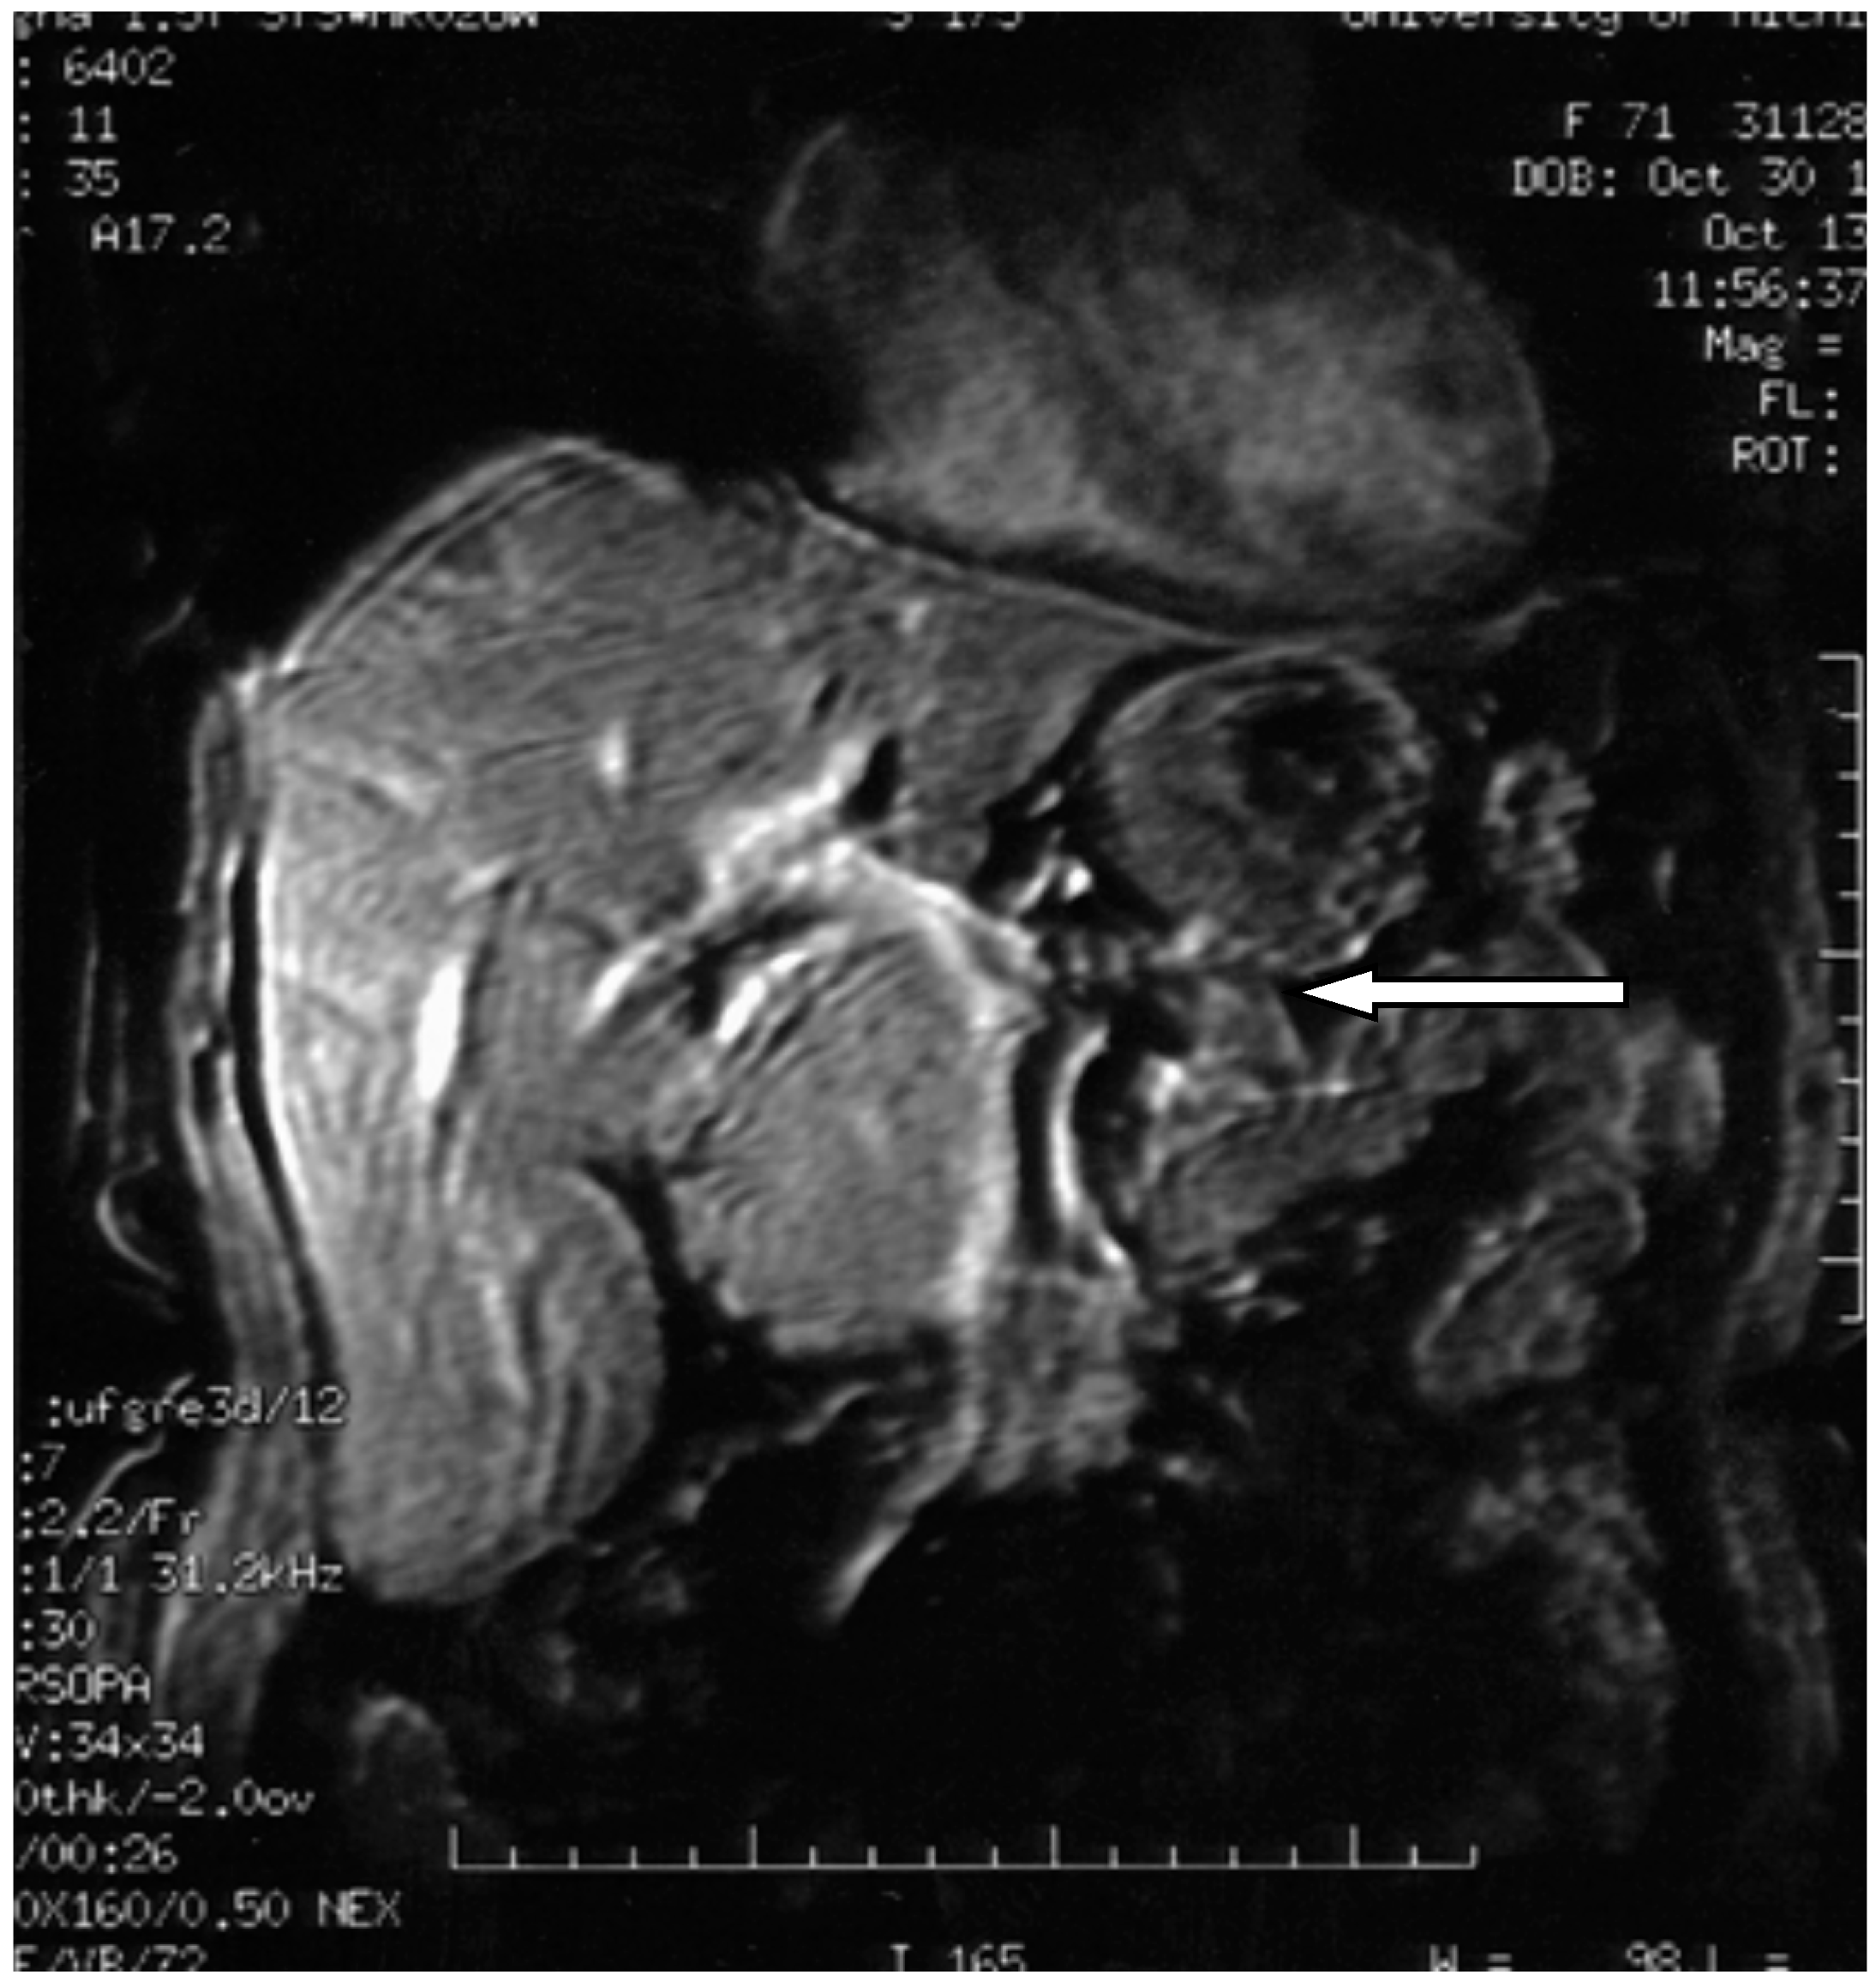

Figure 7.

3D axial magnetic resonance imaging showing pancreatic polypeptide-producing tumors in the head of the pancreas (arrow) [].